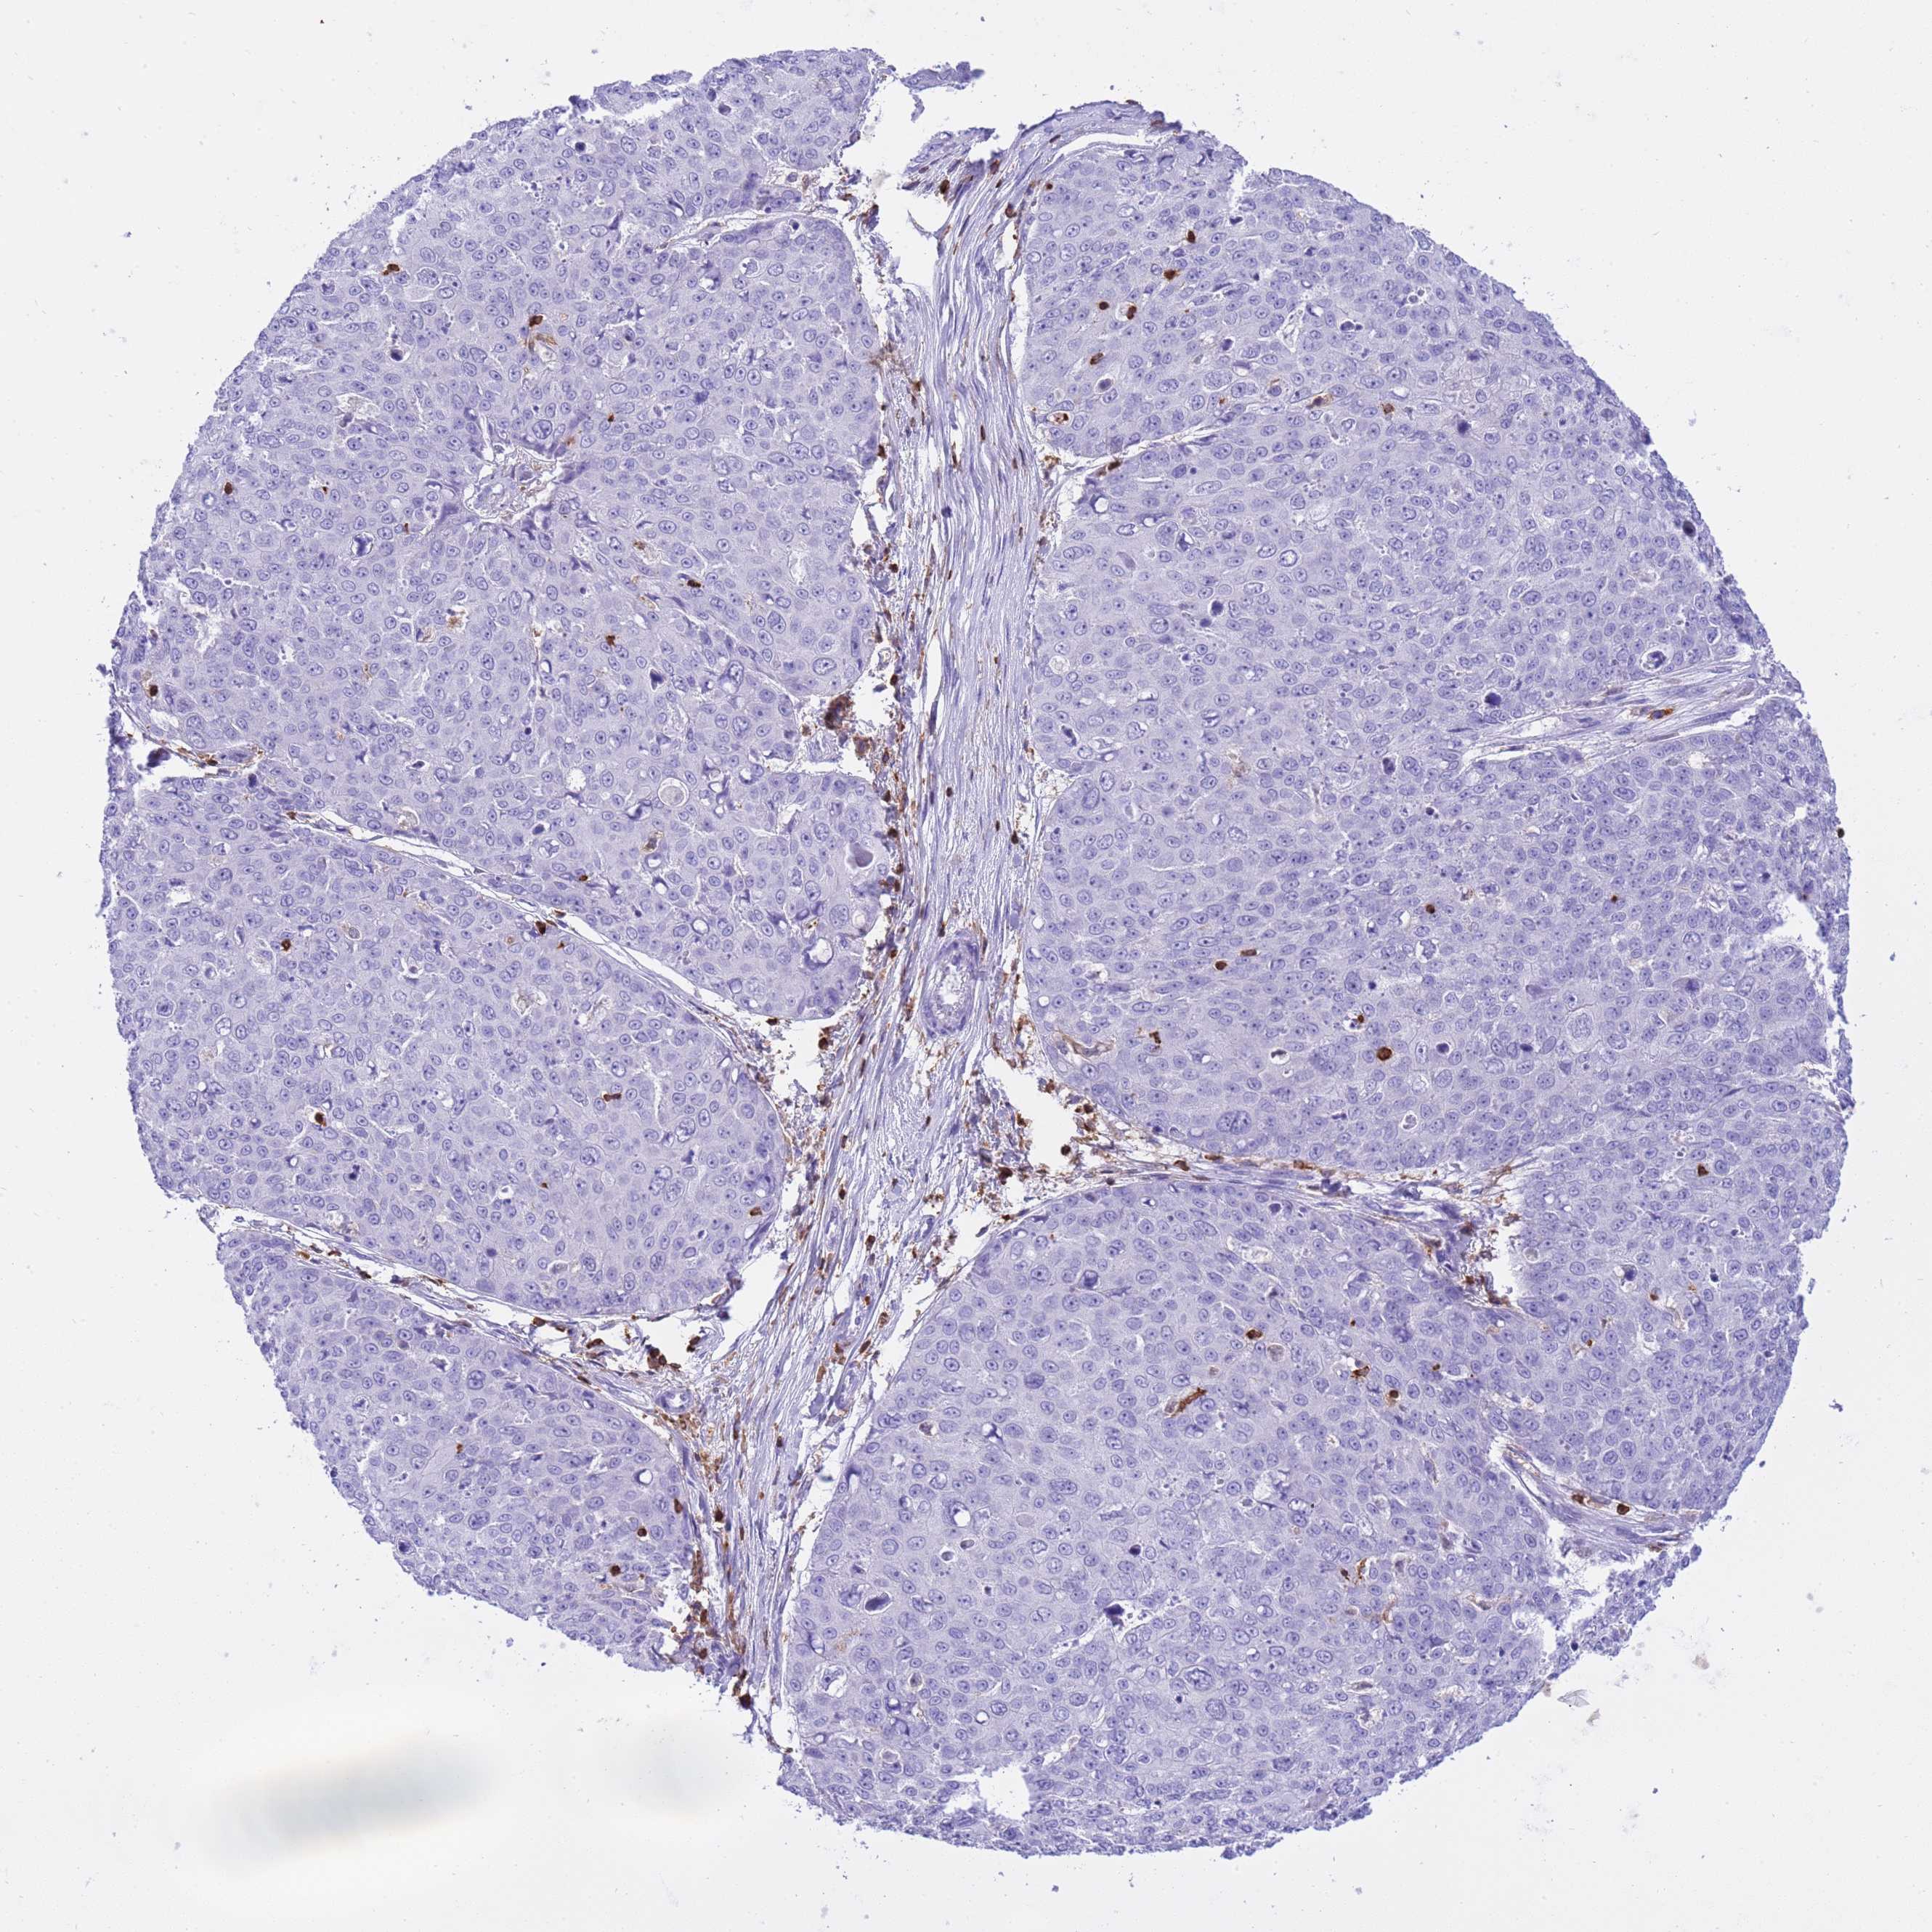

SKIN CANCER - Protein expressioni

A mouse-over function shows sample information and annotation data. Click on an image to view it in a full screen mode. Samples can be filtered based on level of antibody staining by selecting one or several of the following categories: high, medium, low and not detected. The assay and annotation is described here.

Antibody stainingi

Antibody staining in the annotated cell types in the current human tissue is reported as not detected, low, medium, or high, based on conventional immunohistochemistry profiling in selected tissues. This score is based on the combination of the staining intensity and fraction of stained cells.

Each image is clickable and will lead to virtual microscopy that enables deeper exploration of all samples and also displays staining intensity scores, fraction scores and subcellular localization as well as patient and tissue information for each sample.

Antibody HPA046700

Basal cell carcinoma